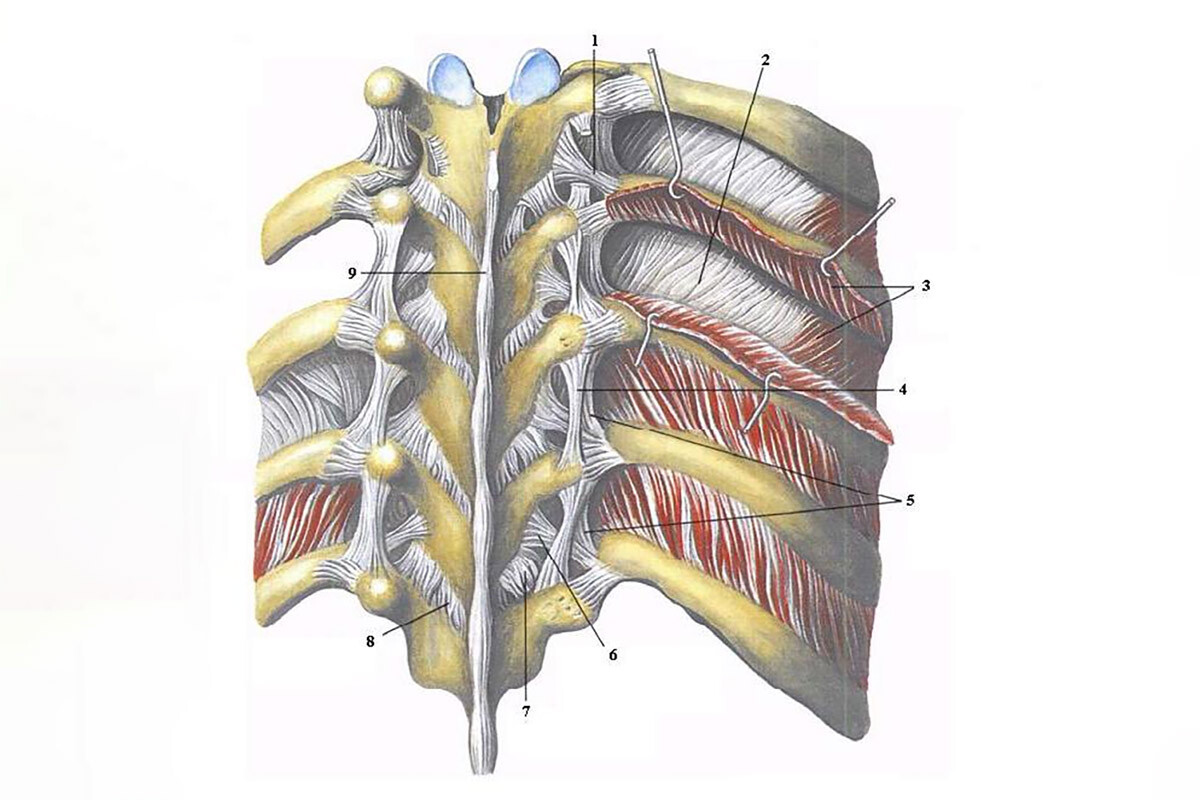

Структура и анатомия синдесмоза: научные иллюстрации